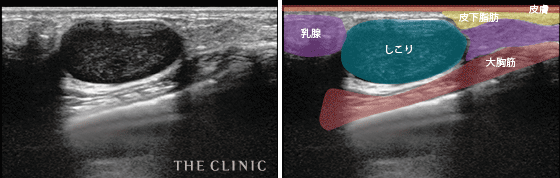

- 大きなしこりとして残ってしまった症例